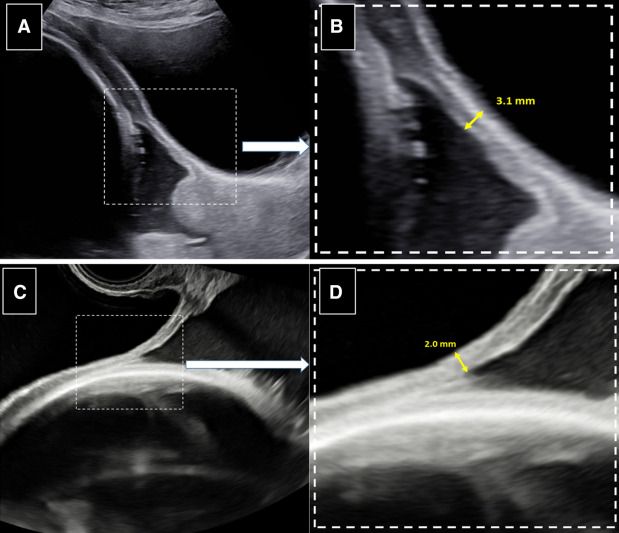

“Uterine scar dehiscence at next pregnancy according to uterine closure technique – Measurement of the lower uterine segment thickness in the third trimester.

Title: Uterine scar dehiscence at next pregnancy according to uterine closure technique

Authors: Stéphanie Roberge, Emmanuel Bujold